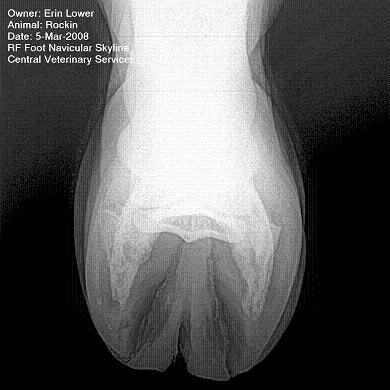

So, Rockin's x-rays were sent to a radiologist and he confirmed "normal" changes in the navicular bones for a horse her age, but slightly more significant ones in the right (sore) foot.

She also has sidebone in both fronts, but apparently that isn't causing any discomfort.

Finally, she has a "small chronic exostosis on the lateral aspect of the proximal phalanx" which, according to the radiologist, shouldn't be causing discomfort but I have read that these can be mild-to-moderately painful... I wouldn't mind another opinion on that.

I will attach as many images as possible from her x-rays (there are many different views). I don't have any pics of the feet as someone deleted them from my camera before I could download them. I'll try to take pics next time she is trimmed. Please, anyone with knowledge of hooves, give any opinions that you might have (especially Dr. O!)

I cannot rule out lesions based on these images but I will take your radiologist's word that he does not see significant lesions. The exostosis on the RF would be above the level of a well conducted PDN which I believed blocked the lameness before?